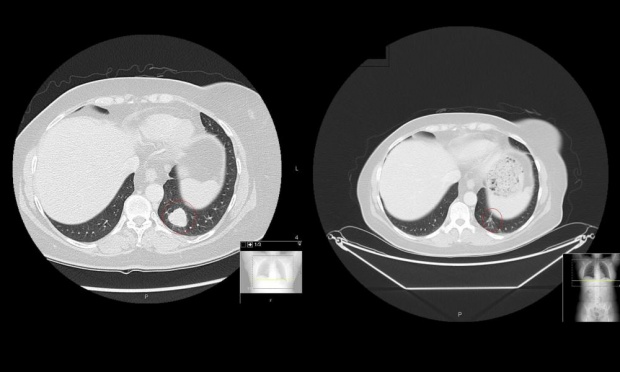

One patient who has benefited from the treatment is former college teacher Vicky Brown, 61, who was told in 2013 she had only months to live after skin cancer spread to her breast and lungs.

She took part in clinical trials at the Royal Marsden hospital last August and within weeks the tumour was eradicated. When it later returned, it was removed with immunotherapy. It has come back a third time but doctors plan to use the same method.